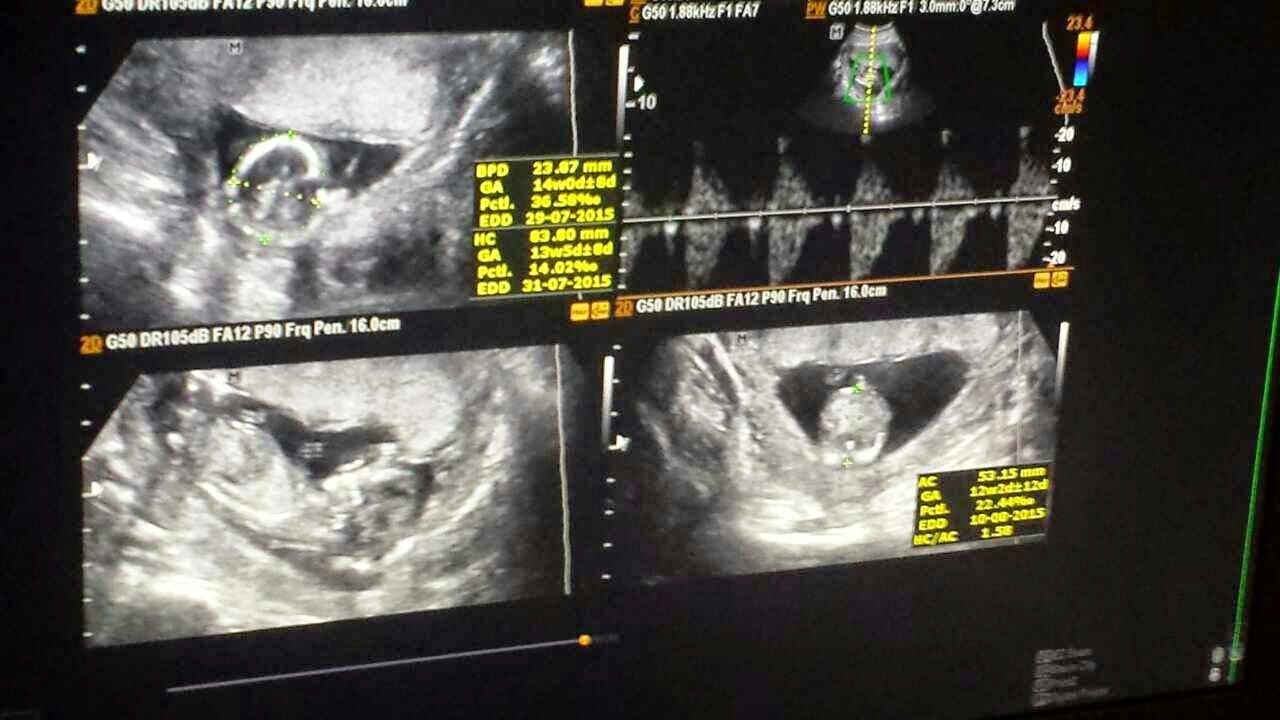

13周,医生说宝宝还看不到性别,只帮我量了胎儿的头部,脚部然后还有体重。宝宝的体重已经有86g了,体长大概是80mm左右。胎儿能够健康的长大做妈妈的真的很欣慰。每一次产检就像做了亏心事那样,觉得很紧张,很担心肚子里的宝宝是否有足够营养和是否有发育完好。每次产检后医生都说ok,心里才能够完完整整的放心。回到家也会开始想些有的和没的。

13周时的宝宝图片: